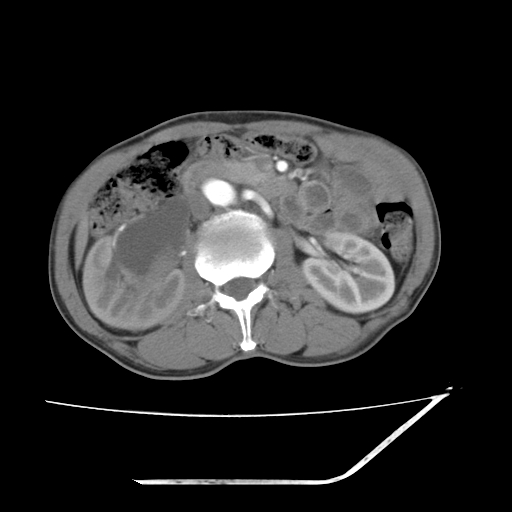

增强

考虑右肾盂癌,肾动脉受侵,右肾功能减退,右肾盂输尿管积水,管壁增厚,考虑种植转移,应该把下面扫完的

支持右侧肾盂癌伴肾静脉瘤栓形成可能性大,右肾结石.肝右叶后段低密度影,不除外转移.

考虑右肾盂癌,肾动脉受侵,右肾功能减退,右肾盂输尿管积水,管壁增厚,考虑种植转移  支持

考虑右侧肾盂癌。右侧输尿管扩张未扫描完。

右肾盂旁ca并肾静脉瘤栓形成/肾功能降低。

右肾结石。

右肾盂癌,肾动脉受侵,右肾盂输尿管积水,管壁增厚,考虑种植转移

右肾盂移行细胞癌并右输尿管中段转移.肾积水.

支持 右侧肾盂癌伴肾静脉瘤栓形成可能性大,右肾结石;肝右叶后段低密度影,不除外转移。

1.右侧肾盂癌伴肾盂积水。

2.肾脏功能减退,原因有:(1)肾动脉受侵。(2)肾静脉受侵(3)肾积水,等。本例,肾动脉显影较好,但受压明显;肾静脉无明显显示,受压或静脉癌栓,下腔静脉腔内未见明显充盈缺损。

3.右侧上段输尿管扩张,原因:(1)积水所致;(2)种植。